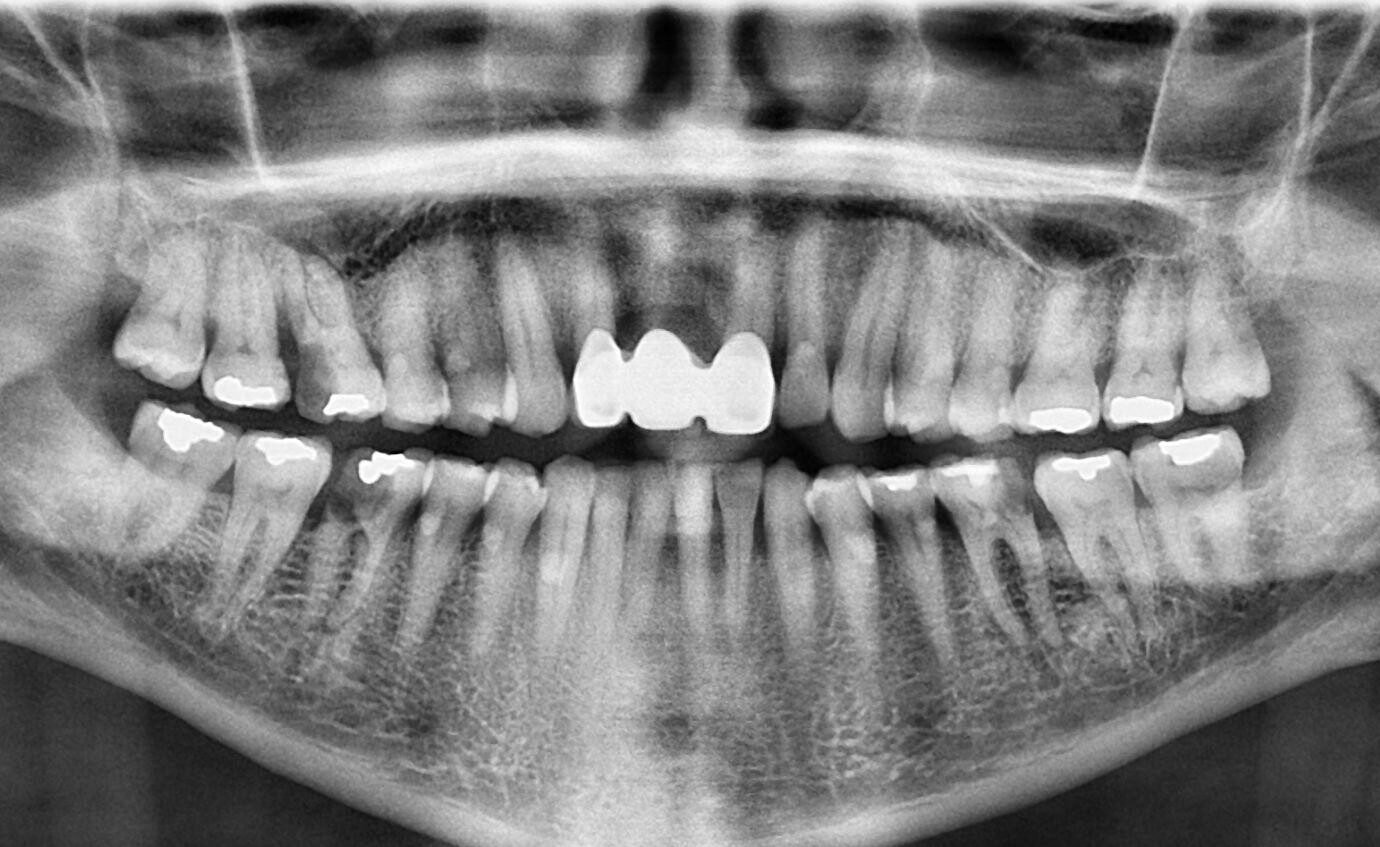

23. What option cannot be selected for the following X ray?

23 / 23